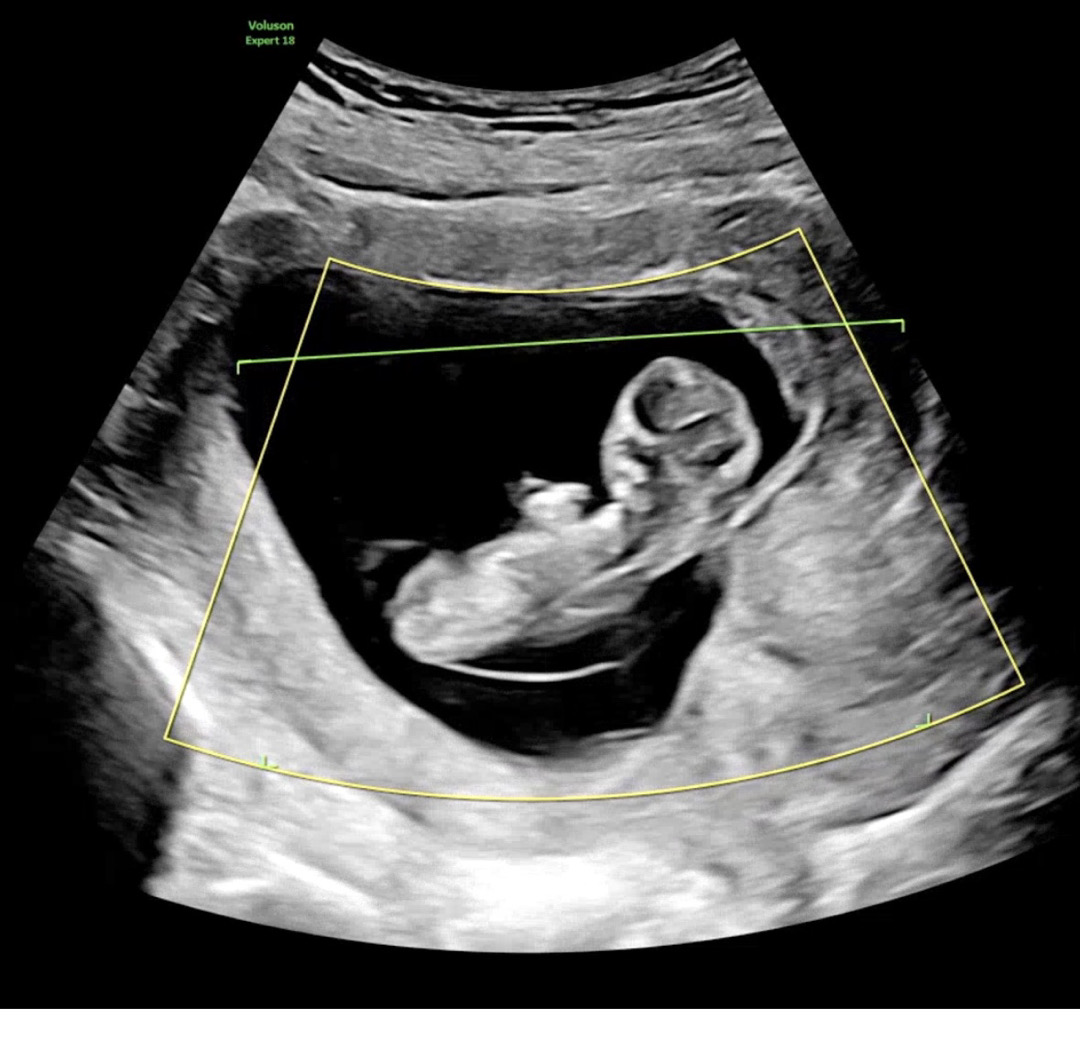

11주차인데 재미삼아 각도법 봐주고가세요 ㅎㅎㅎ

11주밖에 안됐지만 너무너무 궁금해요ㅠㅠㅠ 고슈님들 답변 기다립니다 ㅎㅎ